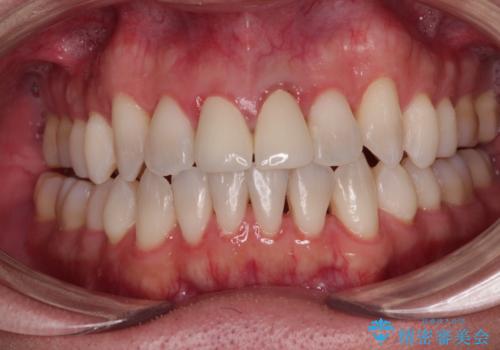

開咬により奥歯のみが接触している状態で、前歯部にほとんど接触のない状態で、奥歯に非常に負担のかかる咬み合わせでした。

治療の期間と費用はかかりますが、初診時とは比べものにならないほど良好な状態にて治療を終えることができました。